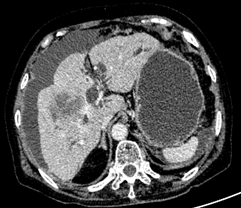

1.肝内型胆管细胞癌

CT、MRI:单发或多发低密度灶,边界不清,增强早期边缘强化,延迟期中央纤维间质进行性向心填充,周围呈相对低密度灶伴周围胆管扩张;薄膜回缩;肝叶萎缩。

肝内胆管细胞癌     肝外胆管细胞癌

病理提示①为肝内胆管细胞癌,②肝外胆管细胞癌